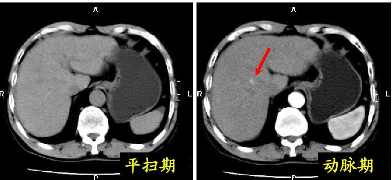

平扫CT是观察病灶的形态、边界和大小等,一般提供观察的信息量比较少。

增强CT是使用对比剂后观察不同时期病变内血供情况,为病变组织与正常组织的对比提供了更多信息,更加有助于疾病的诊断与鉴别诊断。